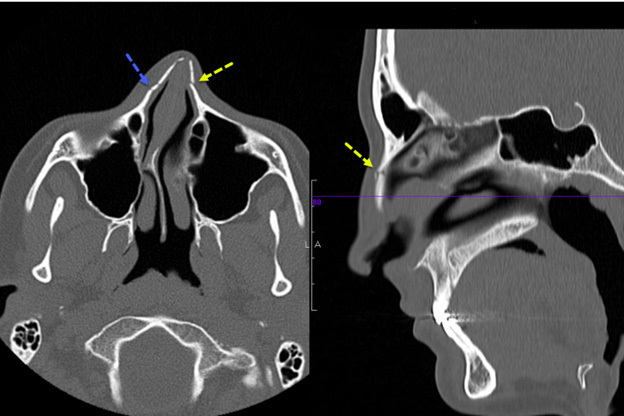

Figure 2 presents an example of a nasal bone fracture on CT scan in a pediatric patient in both the axial and sagittal planes. This example shows an angulated nasal bone fracture with widening of both nasomaxillary sutures.

Figure 2. Computed Tomography Scan of Nasal Bone Fracture |

This image shows an angulated nasal bone fracture with widening of both nasomaxillary sutures. Image courtesy of Mantosh S. Rattan, MD, Radiologist, Orlando Health Arnold Palmer Children’s Hospital, Orlando, FL. |